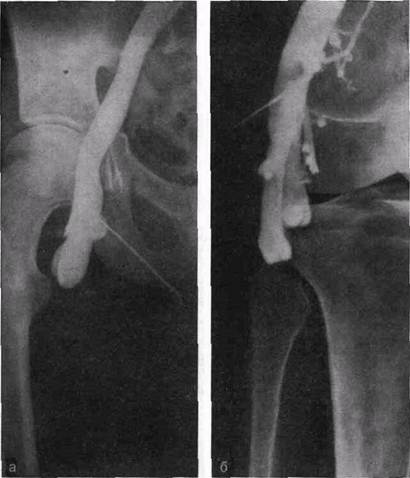

При варикозной болезни повышения внутрибрюшного давления, передающегося на нижнюю полую вену, вызывают в ней не только центростремительный, но и ретроградный кровоток. Под влиянием ретроградного кровотока начинается процесс нисходящей эктазии вен и развития несостоятельности клапанов. Вначале расщиряются нижняя полая,подвздошная вены, затем бедренная, большая подкожная и вены голени. Недоста-точная оснащенность клапанаами наружной подвздошной вены создает предпосылки к дилатации и относительной недостаточности остиального клапана большой подкожной вены или клапанов бедренной вены (рис. 23, а, б).

В клинической практике наблюдаются различные варианты, когда встречается относительная недостаточность тех или иных клапанов, что четко определяется при ретроградной флебогра-фии. Во время пробы Вальсальвы при флебоскопии видно, как контрастированная кровь устремляется ретроградно через недостаточные клапаны большой подкожной и бедренной вен или только по одной из названных вен. В случаях недостаточности клапанов глубоких и поверхностных вен контрастное вещество, введенное посредством пункции в бедренную вену при пробе Вальсальвы, распространяется по глубоким и поверхностным венам до средней трети голени. При полноценных клапанах ретроградного распространения контрастного вещества не происходит. При этом четко контрастируется клапан, ограничивающий ретроградный кровоток (рис. 24, а, б).